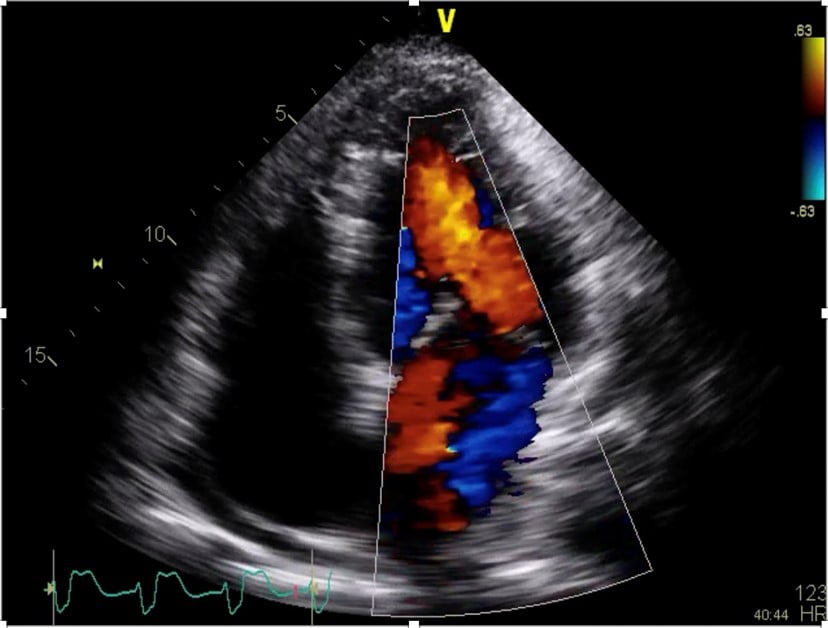

A point-of-care ultrasound was performed to help differentiate the cause of hypoxia and hypotension. The findings were consistent with the sequela of the patients recent RCA occlusion which demonstrated a newly identified flail posterior mitral valve leaflet and severe mitral regurgitation (Figures 1, 2, and 3). Subsequently, the patient was taken emergently to the cath lab for placement of an intra-aortic balloon pump (IABP). The balloon pump was adjusted to maximize the diastolic augmentation and minimize pre-systolic LV afterload to optimize the patient’s cardiac function.1 Once he was stabilized, the patient was taken to the operating room for a mitral valve replacement. After a prolonged hospital course, the patient survived to discharge and was sent to a skilled nursing facility for cardiac rehabilitation.

Figure 3. Apical 4 chamber view of a flail posterior mitral valve leaflet using color doppler demonstrating an eccentric mitral regurgitation.